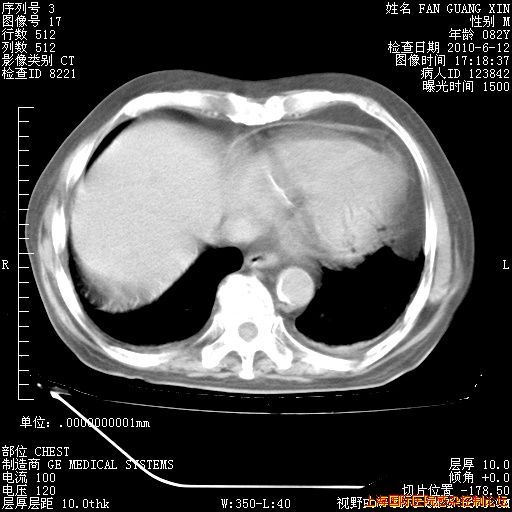

6月12日纵膈窗

整整相隔30天的肺部CT好像有所好转啊。甲强龙减量第3天,需要观察体温。